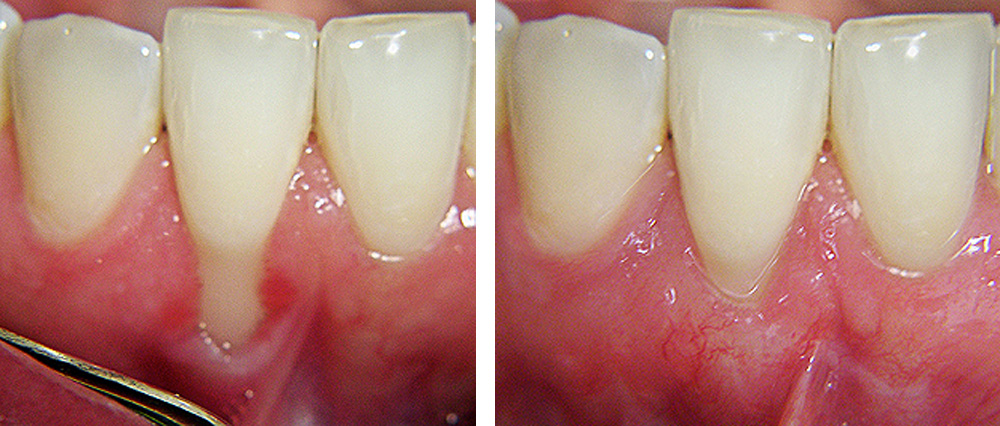

Prekrivanje ogoljelih korijenova zuba

Prekrivanje ogoljelog korijena donjeg centralnog sjekutića prije i poslije